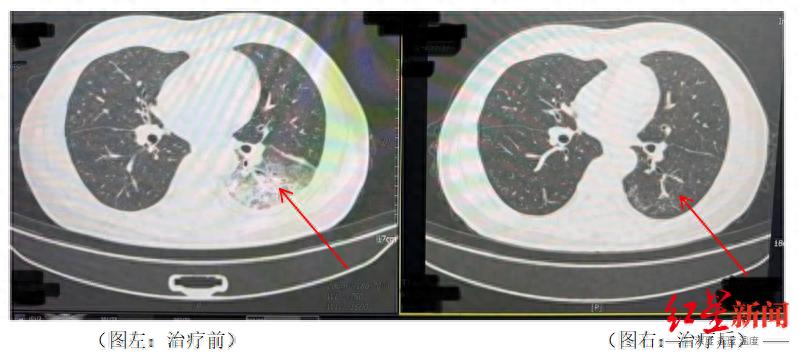

李先生肺部治疗前与治疗后的对比

据悉,开启空调降温3天后,李先生出现了肌肉酸痛、头痛、发热和咳嗽等症状。起初,他以为是吹空调吹感冒了,于是自行服用感冒药,但病情并未好转,反而愈发严重。家人见状,立即将他送往成都市第五人民医院感染性疾病科。胸部CT显示李先生的左肺已出现大面积白色影像,几乎占据一半肺部。经过肺泡灌洗NGS检测,最终确认“罪魁祸首”是嗜肺军团菌。